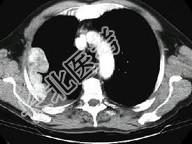

- 单项选择题男,53岁, 胸痛1月余加重2周,CT检查如图, 最可能的诊断为 ( )

A、右侧石棉肺胸膜斑

B、右侧良性胸膜间皮瘤

C、右侧恶性胸膜间皮瘤

D、右侧胸膜转移瘤

E、右侧胸膜弥漫增厚